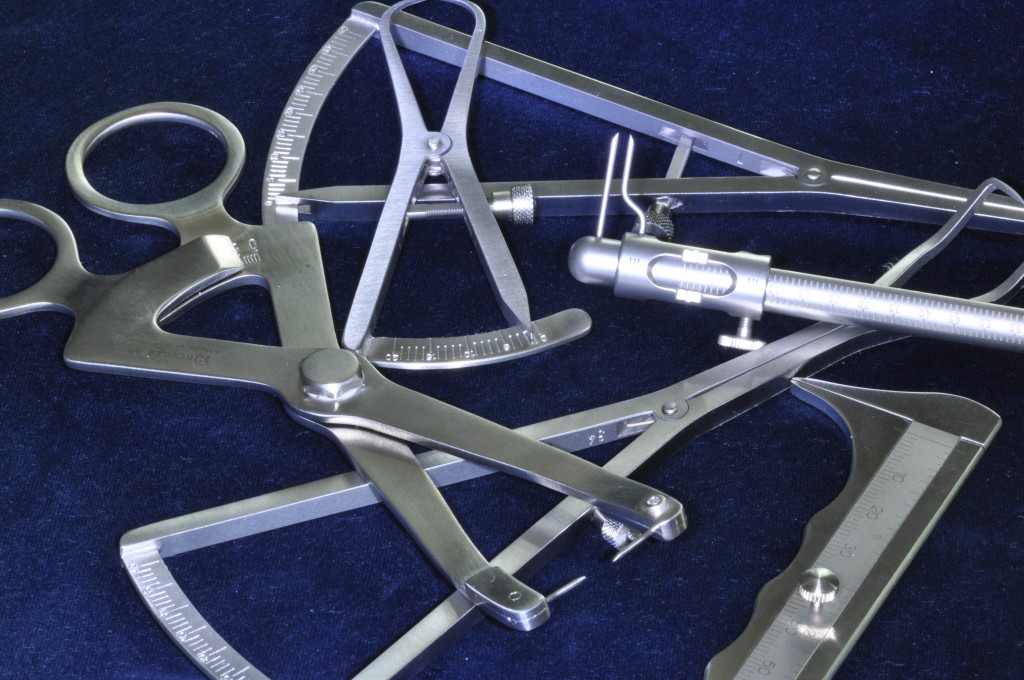

Рекомендуемые инструменты для измерения толщины кости KOHLER - смотрите на сайте medrmo.ru (Рис.2)

Рекомендуемые инструменты для измерения толщины кости KOHLER - смотрите на сайте medrmo.ru (Рис.2)  2. Создание перфораций по всей поверхности принимающего ложа.

Целью этих действий является создание зон, не имеющих антигенных отличий и содержащих повышенное количество собственных жизнеспособных остеобластов и костных стволовых клеток (Рис.4б)  Рекомендуемые инструменты для забора аутокости KOHLER - смотрите на сайте medrmo.ru (Рис.5)

Рекомендуемые инструменты для забора аутокости KOHLER - смотрите на сайте medrmo.ru (Рис.5)  4. Послойное покрытие аутокости композиционными материалами: На первом этапе аутокость укрывают материалом «ОСТЕОМАТРИКС» (Рис.6)